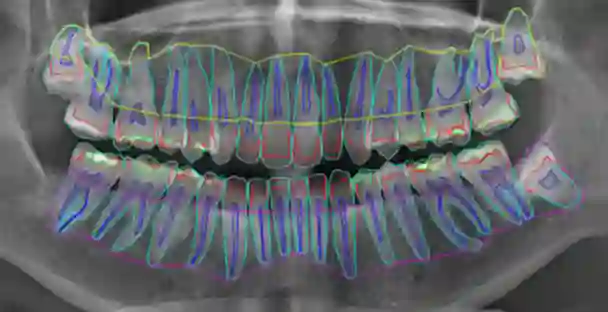

Accurate understanding of anatomical structures is essential for reliably staging certain dental diseases. A way of introducing this within semantic segmentation models is by utilising hierarchy-aware methodologies. However, existing hierarchy-aware segmentation methods largely encode anatomical structure through the loss functions, providing weak and indirect supervision. We introduce a general framework that embeds an explicit anatomical hierarchy into semantic segmentation by coupling a recurrent, level-wise prediction scheme with restrictive output heads and top-down feature conditioning. At each depth of the class tree, the backbone is re-run on the original image concatenated with logits from the previous level. Child class features are conditioned using Feature-wise Linear Modulation of their parent class probabilities, to modulate child feature spaces for fine grained detection. A probabilistic composition rule enforces consistency between parent and descendant classes. Hierarchical loss combines per-level class weighted Dice and cross entropy loss and a consistency term loss, ensuring parent predictions are the sum of their children. We validate our approach on our proposed dataset, TL-pano, containing 194 panoramic radiographs with dense instance and semantic segmentation annotations, of tooth layers and alveolar bone. Utilising UNet and HRNet as donor models across a 5-fold cross validation scheme, the hierarchical variants consistently increase IoU, Dice, and recall, particularly for fine-grained anatomies, and produce more anatomically coherent masks. However, hierarchical variants also demonstrated increased recall over precision, implying increased false positives. The results demonstrate that explicit hierarchical structuring improves both performance and clinical plausibility, especially in low data dental imaging regimes.